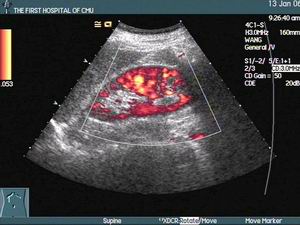

3.治療原發病、消除誘因如高血壓者採用降壓措施,快速異位心律失常要糾正心律失常;二尖瓣狹窄者施行緊急二尖瓣球囊成形術或二尖瓣分離術。